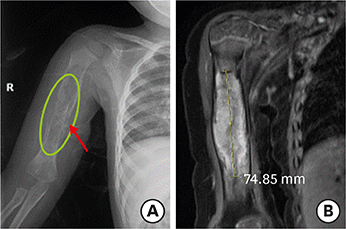

A 4-year-old boy was referred to the department of pediatric surgery at Seoul National University Children's Hospital due to an abdominal mass found on an abdominal ultrasound. He was previously diagnosed with LCH on his right humerus (Fig. 1). At the first diagnosis, the child reported arm pain and fever which had persisted for a month. He was treated at another hospital with chemotherapy, comprising vinblastine and prednisone, from March 2018 to June 2019. The child underwent follow-up, which involved monthly radiography of his humerus and bone scans every 3 months. After staring of 15 months chemotherapy, a routine abdominal ultrasound was performed to potentially identify any new lesions in the abdomen. On the imaging taken on May 31, 2019, an abdominal mass was detected, and ultrasound-guided biopsy was performed. Pathology results initially suggested that the mass was ganglioneuroma. The child showed no specific symptoms, such as abdominal discomfort, at the time of the ultrasound. The patients' neuron-specific enolase level was 21.38 ng/mL (normal range: 0–16.3 ng/mL) and ferritin level was 9 ng/mL (normal range: 16–400 ng/mL).

Fig. 1

Right humerus X-ray (A) and upper arm MRI (B). The X-ray shows an osteolytic lesion on the right humerus with a lamellated periosteal reaction (A). MRI of the right upper arm shows a 7.5×1.4×1.5 cm enhancing osteolytic mass replacing right humerus diaphysis with extensive soft tissue edema (B). This lesion was diagnosed with Langerhans cell histiocytosis by ultrasound-guided biopsy.

MRI, magnetic resonance imaging.